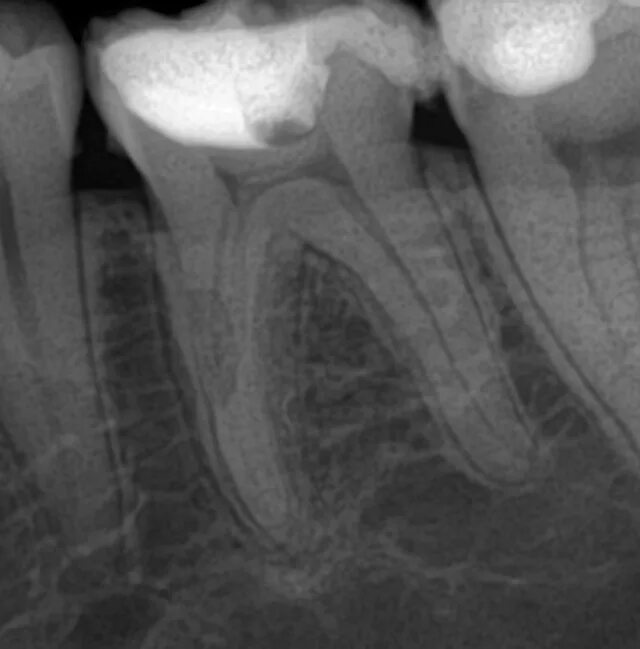

Признаки резорбции